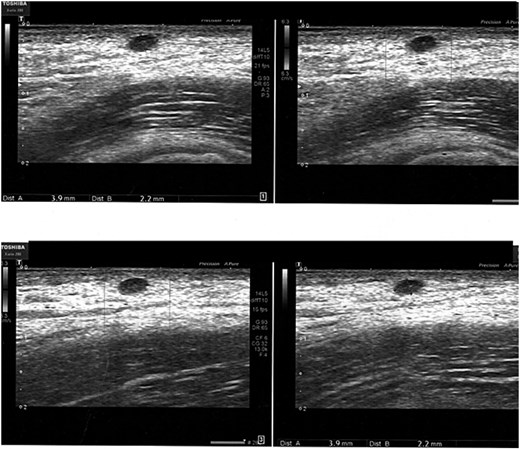

We present the case of a 48-year-old female patient with a medical history of hypothyroidism, treated with levothyroxine, and fibrocystic mastopathy, which is under ongoing follow-up. In 2021, the patient developed a subcutaneous swelling in the right axillary region. Initially, it was asymptomatic and showed no signs of inflammation. During the same year, two ultrasound scans of the axillary area were performed. Both scans revealed a hypoechoic lesion with regular borders, without signs of lymph node involvement, and the initial diagnosis was a sebaceous cyst (Figs 1 and 2).

Ultrasonographic examination performed in the right axillary cavity shows in the superficial planes a centimetric oval, hypoechogenic, regular-edged shape to be varably referred to sebaceous cyst. Loco-regional lymph nodes in the deep planes, diam max 17 mm.

The clinically appreciable formation in the right axillary site corispondes to a todouble, well-defined contour, hypoechogenic image, lacking colorimetric signal, compatible for sebaceous cyst of 3 x 2 mm diam. Absence of locoregional lymph node hyperplasia.

In 2023, the patient began experiencing increased local discomfort, with symptoms worsening around her menstrual cycle. A follow-up ultrasound in July 2023 showed no significant changes compared to the previous exams.